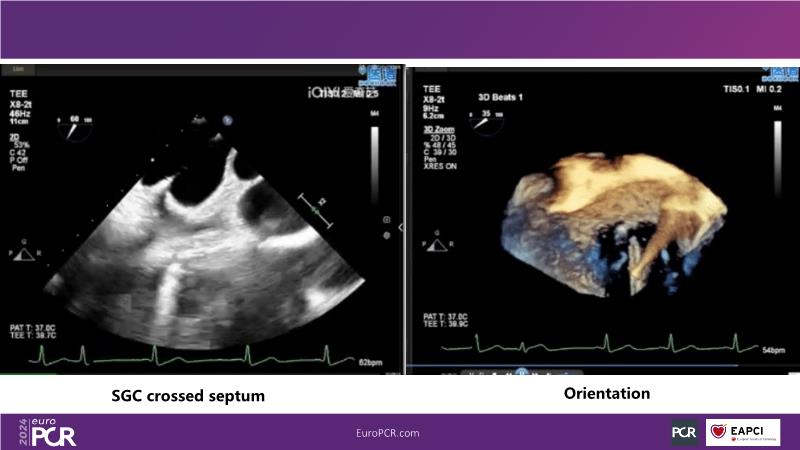

Watch this session to gain insights into the clinical evidence of mitral TEER therapy for the Asian population, learn techniques for implanting a MitraClip in patients with challenging anatomy, and understand how to use the four clip sizes for optimal outcomes. The session also covers educational aspects of clipping in dextrocardia, the benefits of reserve bending of the transseptal needle for tenting and puncture, new steering maneuvers for dextrocardia patients, and the importance of understanding anatomy and collaborating closely with the echo team for success.